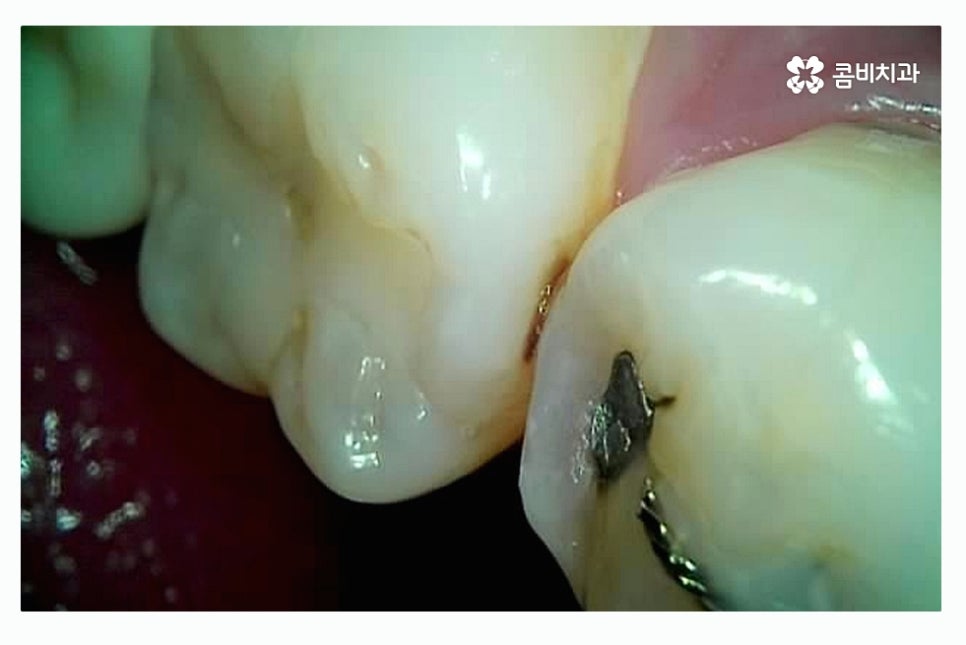

성인 이후에는 충치의 발생률이 통계적으로 줄어들기는 하지만

치아 사이 충치가 발생되는 사례가 많고

이미 과거에 충치 치료를 했던 레진, 인레이 안에 2차 충치가

발생되는 경우도 있기 때문에 이러한 사례의 경우

치과를 주기적으로 방문하지 않는다면 놓치기 쉬울 수 있는데요.

인접면 충치는 초기 발견이 어렵고 치아끼리 맞닿아 있기 때문에

노출이 잘되지 않아서 눈으로도 보기 어렵고

엑스레이를 통해서도 초기에는 확인이 어려운 경우가 많기 때문에

예방을 하는 것이 중요하며 인접면 충치가 발생하면

신경(치수)과도 가깝기 때문에 충치가 조금만 깊어져도

신경치료를 해야 할 가능성이 높아 치아의 수명이 줄어드는 결과를 초래할 수 있어요.